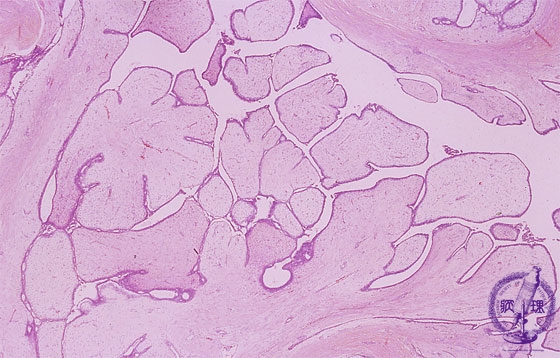

Microscopic image(HE stain, low power view):Both proliferating epithelial and stromal cells form leaf like structures. Proliferative stroma associated with edematous changes.